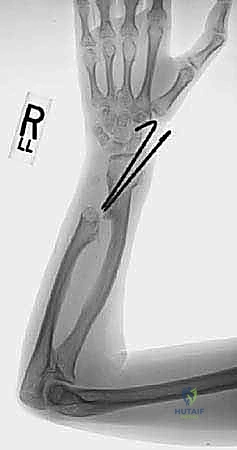

Forearm deformity is a prominent and debilitating manifestation, occurring in 30% to 60% of MHE patients. The paired-bone anatomy of the forearm makes it uniquely susceptible to asynchronous longitudinal growth. Because 80% of ulnar longitudinal growth occurs at the distal physis—which is disproportionately affected by osteochondromata—the ulna frequently becomes tethered and shortened. This relative ulnar shortening forces the continuously growing radius to bow (typically convex dorsoradially), increases ulnar variance, alters the radial articular angle, and invariably leads to progressive radial head subluxation or frank dislocation.

Surgical intervention for MHE forearm deformities is dictated by the magnitude of the deformity, the trajectory of progression, the degree of functional impairment, and the status of the radiocapitellar joint. The Masada classification remains the universally accepted framework for categorizing these deformities and establishing a surgical algorithm.

- Type I: The most common variant. Characterized by an osteochondroma of the distal ulna causing primary ulnar shortening and secondary radial bowing. The radial head remains anatomically located.

- Type IIa: Characterized by ulnar shortening with radial head dislocation. The primary osteochondroma is located at the proximal radius, directly impinging on the PRUJ.

- Type IIb: Characterized by ulnar shortening with radial head dislocation. The primary osteochondroma is located at the distal ulna, causing severe tethering and proximal failure (dislocation).

- Type III: Characterized by an osteochondroma of the distal radius causing relative radial shortening and positive ulnar variance (less common).

Standard orthogonal radiographs (true AP and lateral) of the wrist, forearm, and elbow are mandatory. Bilateral imaging is strongly recommended to establish the patient's baseline anatomy, acknowledging that MHE is typically a bilateral, albeit asymmetric, disease. Critical radiographic parameters to quantify include:

* Ulnar Variance: Measured as the distance between the distal articular surface of the ulna and the lunate fossa of the radius.

* Radial Articular Angle (RAA): The normal RAA is typically 15 to 30 degrees. In MHE, this angle pathologically increases due to distal ulnar tethering and relative radial overgrowth.

* Maximum Radial Bowing: The magnitude and exact diaphyseal apex of the radial bow must be calculated to dictate the site of a potential corrective radial osteotomy.